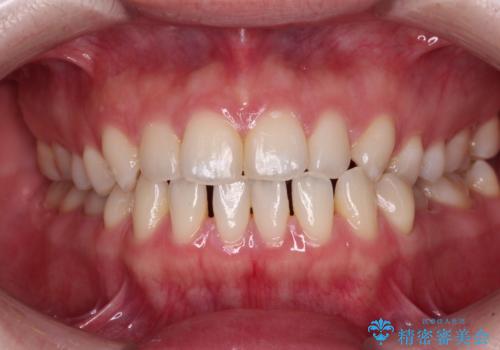

すきっ歯をインビザラインできれいな歯並びに改善

- 前歯の隙間を気にして来院された患者様です。

隙間や叢生の程度はそれほど著しいものではなかったので、インビザラインでもワイヤー矯正でも対応可能でしたが、極力目立たない装置を希望されたため、インビザラインにて矯正治療を行うこととしました。